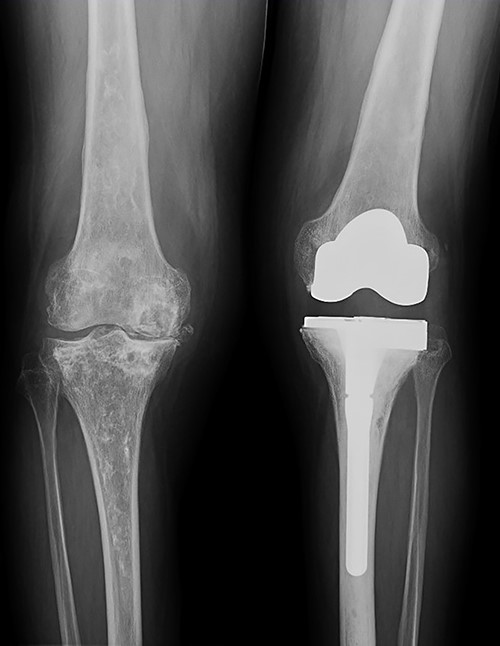

At this point, the patient was recovering from a respiratory infection with multiple admissions and relapses, with CD4 cell count of 146 cells/ml. Therefore, conservative treatment was recommended, but pain control was insufficient. After 8 months she was admitted to the emergency service in a wheelchair due to intractable acute pain without prior trauma in the left knee, which prevented weight-bearing. New standing X-rays of the left knee showed collapse of the external tibial plateau (Fig. 2). At this time, the patient exhibited acceptable medical control, with CD4 240 cells/ml and undetectable viral load.

Standing X-rays of the left knee 8 months later showed collapse with depression of the external tibial plateau and associated bone defect that caused 28° valgus deformity.